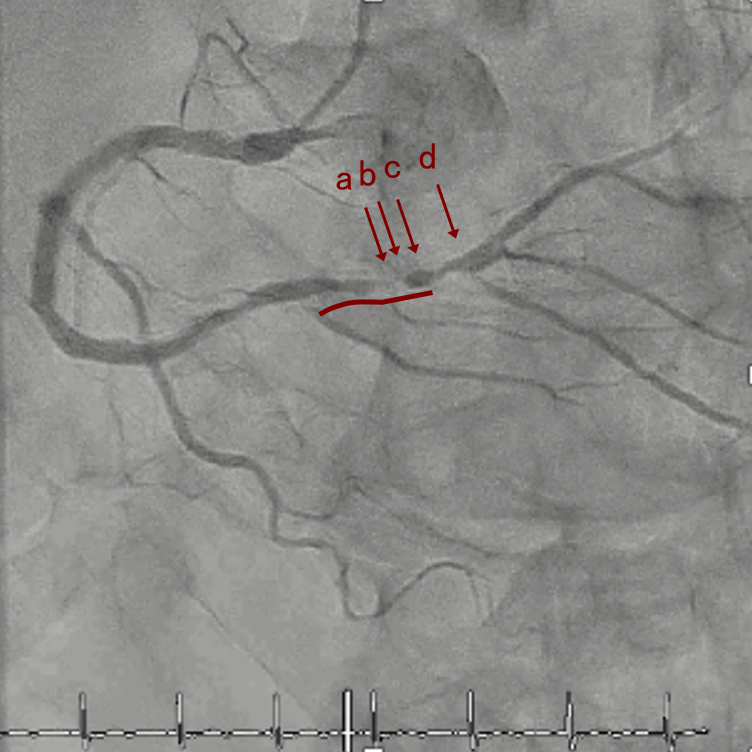

OAS low speedによる引きのsandingを3回行いIVUSを確認するとa-cでは心筋側側へのOASによる良好なbias変化と、それに伴いdの健常側への危険なbias変化を認めた。

そのためcでIVUSマーキングを行い、その点より引きで赤線のpinpoint OAS high speedを行い、dに関してはinjury回避のためにOASを当てない方針とした。

引き続き造影で確認してpinpointで引きのOAS high speedを3回さらに追加のためcでIVUSマーキングを行い、その点より引きで赤線のpinpoint OAS high speedを行い、dに関してはinjury回避のためにOASを当てない方針とした。

OASを行うたびに徐々に心筋側側にwire bias変化をきたし、石灰化病変部に関してはそれが良い変化となっているが、distal reference (d) に関してはinjury riskの高いbias変化となっていった。

OASでsandingを繰り返すことでwire biasは大きく変化することがある。

その変化は良好な変化のこともあれば危険な変化のこともある。

本症例は石灰化病変部に関してはsandingを行うことで石灰化内に食い込み、良好なbias変化をきたした。しかし、その一方でwire biasが心筋側側にかかることでdistal referenceで健常側への危険なbias変化をきたした。

OASの後、繰り返しIVUSを行うことでwire bias変化を捉えることができる。またIVUSマーキングすることで、ピンポイントに削りたいところだけを安全に削ることができる。